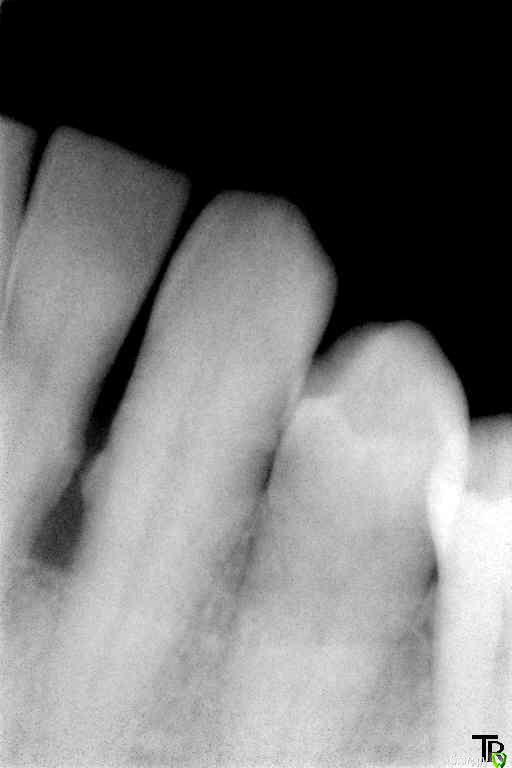

Витторио Орлионе Опубликовано 14 февраля, 2016 Поделиться Опубликовано 14 февраля, 2016 12.02.2016 Обратился Мужчина 72 года рождения с жалобами на боли и припухлость в области фронта нижней челюсти, на зубах налёт от стоматотофита, рецессия десны и резорбция кости,подижность 2 степени у зубов 4.2, 4.1 и 3 степени у зубов 3.1 и 3.2 десна вздулась в области зуба 3.2. Перкуссия да и просто прикосновения вызывали жуткие боли. Вколов 2 карпулы ультракаин дс форте инфильтративно + лидокаин, так и не обезболились, хотя губа занемела. Промыл хлоргексидином и оставил смесь из метрогила и трихопола под дессной, пациент при этом от боли вжимался в кресло. А как встал, ноющие боли прошли, а до зубов по прежнему не дотронуться. До посещения начал пить аугментин. Был 2й день приёма. Пришёл 14.02. Не болит, припухлость спала. 2 карпулы ультракаина дс форте не обезболилил. манипуляции повторил. Отправил до наступления реммиссии. Снимки прилагаются. Вопросы:Как обезбаливать в таких случаях?Удалять ли 3.2?Обязателен ли открытый кюретаж?Да и вообще как бы вы его вели? Ссылка на комментарий